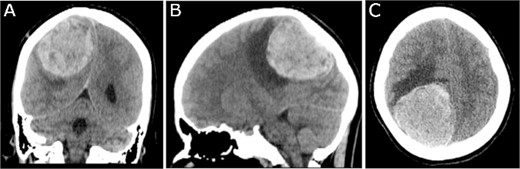

A 19-year-old woman presented with 2 months of intractable holocephalic headaches associated with nausea, occasional emesis, and generalized weakness which worsened over the 5 days preceding presentation. She had no past medical history and was not taking any regular prescribed medications. A computed tomography (CT) head (Fig. 1) revealed a right parietal mass measuring 6.2 × 5.5 × 5.8 cm. Her magnetic resonance imaging (MRI) re-demonstrated a large right parietal extra-axial mass as well as similar lesions in the right temporal lobe, with diffuse increased T1 signal without corresponding enhancement (Fig. 2).

Preoperative CT imaging; (A) coronal, (B) sagittal, and (C) axial CT scans show a large right parietooccipital lesion with vasogenic oedema, mass effect, and midline shift.